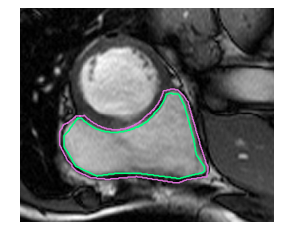

The 48 patients were split equally into three parts such that one part is for training and the other two for testing by the organizers. Each patient’s MRI includes between 200 and 280 images, with 20 images per cardiac cycle. A sample of the available dataset is as shown in Figure 1. It shows both endocardial and epicardial contours marked on it in green and pink colors respectively.

Figure 1: Typical image from dataset with endocardial and epicardial walls [12]. The endocardial contour is shown in green colour and the epicardial in pink colour (Best viewed in colour).